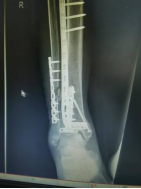

4.胫腓骨粉碎性骨折—MIPO技术